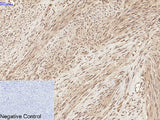

Applications WB,  IHC-p,  IF

IHC 1:100-1:300